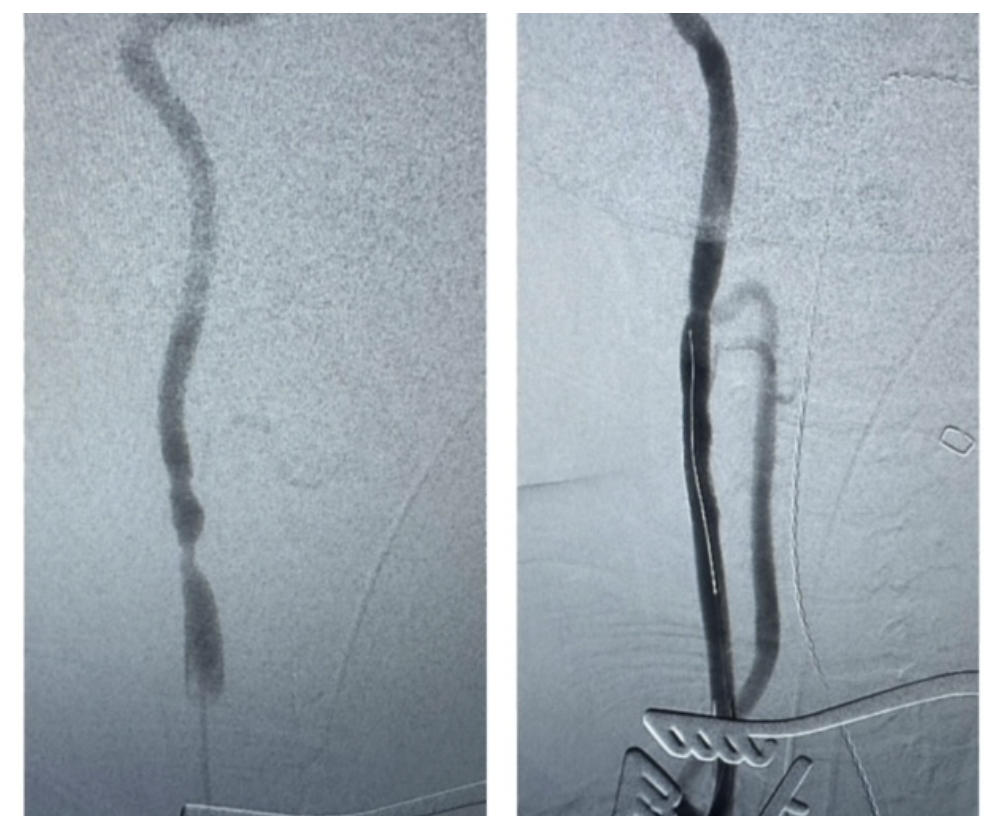

The procedure was done under general anesthesia under flow reversal using the Enroute system (Silk Road Medical). Noninvasive cerebral oximetry was used for neuromonitoring during the case. A cut-down to expose the proximal right CCA at the base of the neck between the 2 heads of the right sternocleidomastoid muscle was made. The patient was systemically anticoagulated. The right CCA was accessed with a micropuncture system, and the sheath of the micropuncture system placed in the CCA was used to perform angiography of the carotid bifurcation vessels. The ECA was occluded and high-grade stenosis of the ICA was seen. Stopping short of the lesion, the 8F Enroute arterial sheath was placed over the provided 0.038-in stiff wire and a stable platform was achieved. The arterial sheath was connected to the 8F venous sheath placed in the contralateral common femoral vein and flow reversal was confirmed. The systolic BP was raised to 160 mm Hg and the right CCA was clamped. There was no change in cerebral oximetry on either side with carotid clamping. The .014-in guidewire was advanced across the lesion into the petrous part of the ICA, and a 7 x 30-mm Enroute stent was placed across the stenosis in the ICA and proximal CCA and deployed. The stent was post-ballooned using a 4 x 30-mm balloon with excellent stent expansion on the completion angiogram. In Figure 3, the image of the implanted stent is shown on the right, with preprocedural imaging depicted on the left.